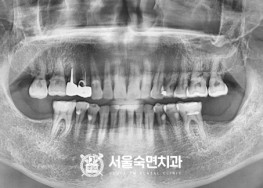

임플란트-치료-전후사진